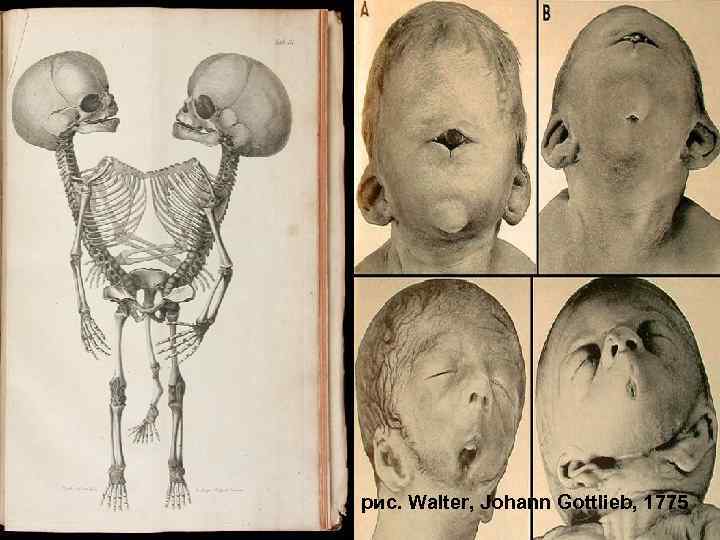

127 рис. Walter, Johann Gottlieb, 1775

Циклопизм, "жаберные щели" 128